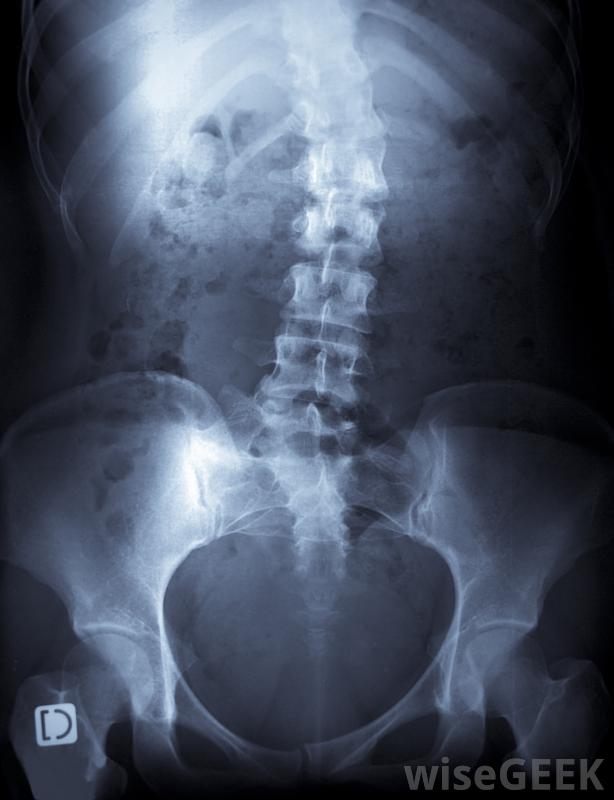

脊柱侧凸是脊柱的一种侧弯或侧弯,它是一列被称为"椎骨"的小骨柱,相互堆叠在一起;它从颈部后部开始,一直延伸到臀部顶部。虽然每个脊柱都有自然的前后曲线,但如果在青春期脊柱生长时形成了侧弯,则可以使用脊柱侧凸后支具来矫正曲线。如果没有矫正,明显的曲线可能会导致不平衡、肌肉无力、疼痛,甚至极端情况下会干扰呼吸。

脊柱侧凸会导致脊柱弯曲。脊柱侧凸背带是典型的治疗曲线达到25度时使用的方法。一旦确定这是一个合适的治疗过程,脊柱侧凸背托通常会一直戴到脊椎停止生长。这通常意味着支架要戴好几年。大多数支架都是在任何时候戴的,包括在睡觉的时候,虽然它们可以在洗澡时取下,但这一点很重要,因为这样做的目的是使脊柱始终保持适当的对齐,这有助于脊椎的直线生长。然而,有些患者可能会被允许每天移除支架一到两个小时来参加游泳等活动